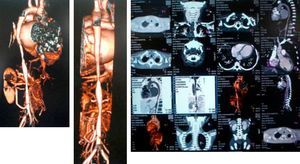

A computed tomography scan revealed hypoplasia of the right vertebral artery (V4), left subclavian stenosis and narrowing of the descending aorta with arteritis data on the wall, yuxtadiafragmática and transverse diameters of 4.5–5.0mm. Were also stenosis in the origin of the superior mesenteric artery (3.3mm) and significant stenosis in the origin of the right renal artery (Fig. 1).